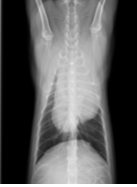

細胞診の検査結果において、胸腺腫が疑われました。腫瘍のサイズがかなり大きかったため、外科手術の前に減容積を目的としたステロイドの内服薬による治療を開始しました。

幸いステロイドにより、減容積の効果が高く得られたので、そのまま外科手術にて腫瘍摘出術を行いました。

↑ステロイド服用後の胸部レントゲン